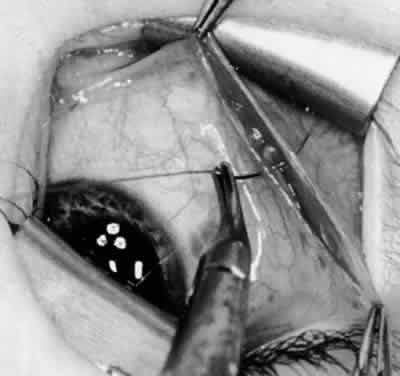

Fig. 11. Sutures are placed into the insertion of the inferior oblique muscle before it is sectioned from the globe for the recession procedure.

Fig. 12. An Aebli scissor is placed beneath the inferior oblique muscle insertion before it is sectioned from the globe.